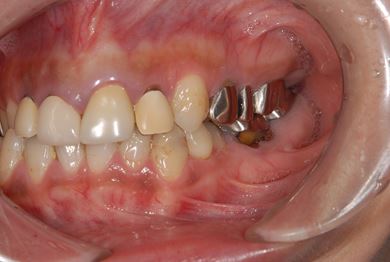

| 性別/年齢 | 女性 / 38歳 | ||||||||||||||||||||||||||||||||

| 主訴 | 奥歯の痛み(虫歯)。銀歯の所だと思います。なるべく痛くない治療がいいです。 | ||||||||||||||||||||||||||||||||

| 治療方針 | セラミック治療にて、審美的回復を行う。 | ||||||||||||||||||||||||||||||||

| 治療内容 | ハイブリッドセラミッククラウン1本(ハイブリッドセラミック用土台1本) | ||||||||||||||||||||||||||||||||

| 総治療費 | 96,600円 | ||||||||||||||||||||||||||||||||

| 治療期間 | 2ヶ月 |